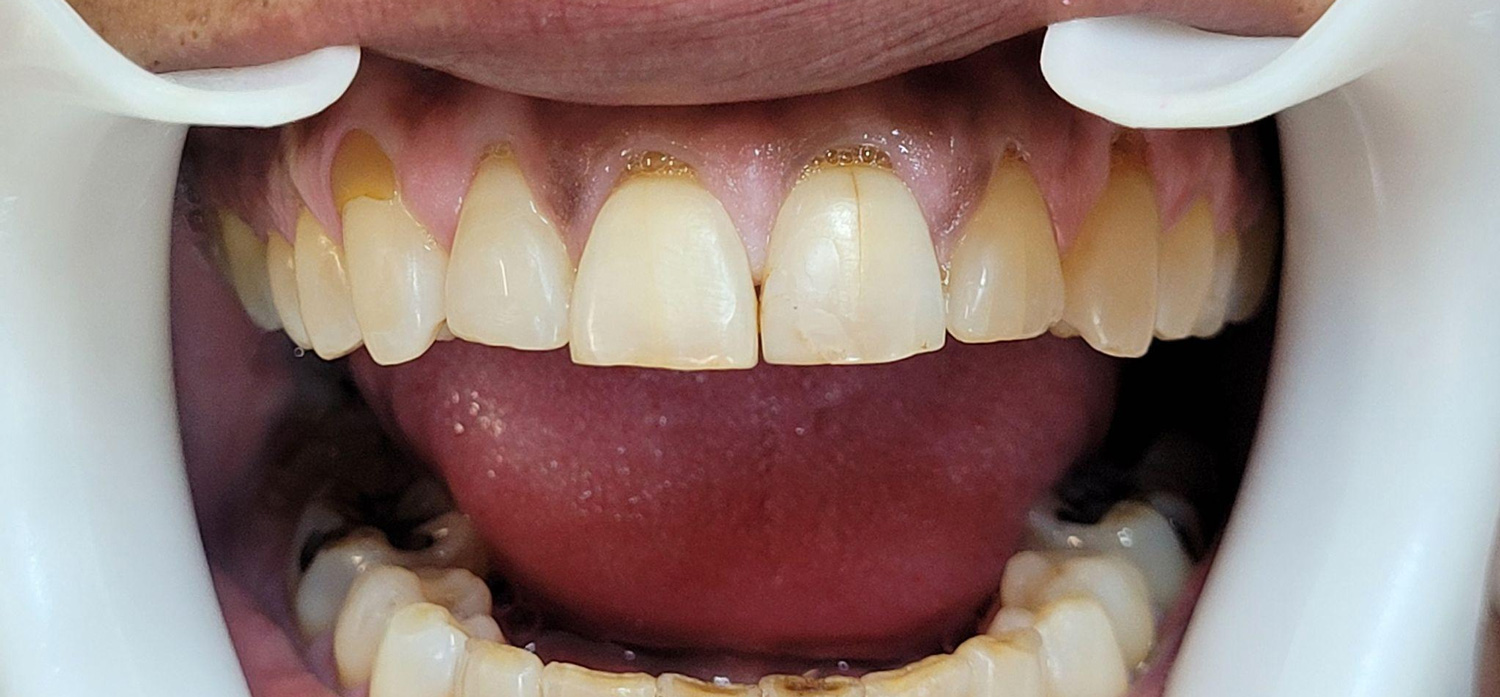

Initial clinical presentation.